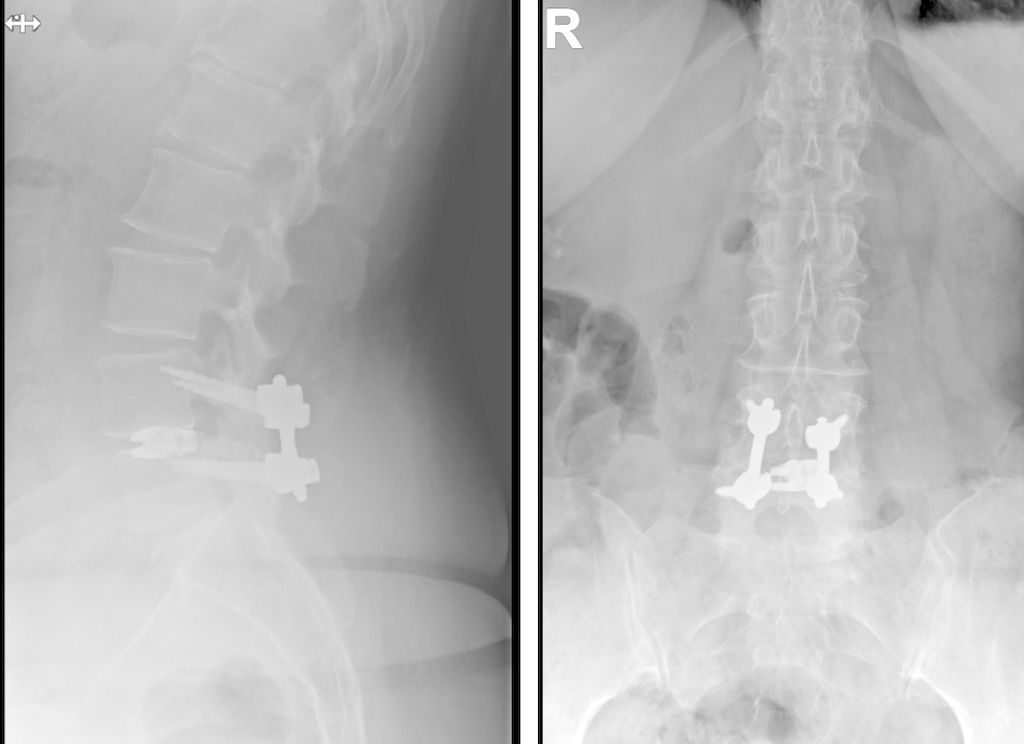

TLIF über Mittellinienzugang mit Schrauben in „cortical bone trajectory“. Bei der 63-jährigen Patientin bestand eine degenerative Spondylolisthese Meyerding Grad I mit Facettengelenkszysten und Wirbelkanalstenose (Abb. 8). Klinisch bestanden Lumboischialgien mit Ausstrahlung dem Dermatom L5 bds. entsprechend. Es wurde ein Mittellinienzugang durchgeführt und zuerst wurden navigierte Schrauben in „cortical bone trajectory“ platziert (Abb. 9). Anschließend erfolgten eine Facettektomie L4/5 links und eine Dekompression des Wirbelkanals. Abbildung 10 zeigt, dass der Hautschnitt aufgrund der mittelliniennahen Schraubenköpfe klein gehalten werden kann. Klinisch wurden die lumbalen Schmerzen wie ausstrahlende Beschwerden 1 Jahr postoperativ annähernd vollständig behoben, die korrespondierende Röntgenkontrolle ist in Abbildung 11 dargestellt.